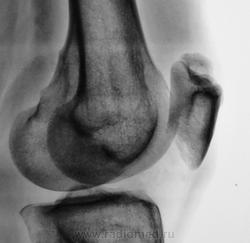

Несросшийся апофиз надколенника, деструкции не вижу

Такое развитие надколенника. Хотя может быть и травматический разрыв фиброзных сращений.

А, может быть просто пателла бипарцита?

Можно уточнение ? Край основной массы надколенника неровный, углы заострены и щель выглядит неравномерной -это обычная картина при удвоении надколенника ?

И мне это не понравилось. И по боковой - впечатление о смещении фрагмента.

Мужчина 39 лет, жалоб нет. Обратил внимание на разницу с другим коленным суставом (выпирает). Второй сустав на снимке без изменений. Травм утверждает, что не было.